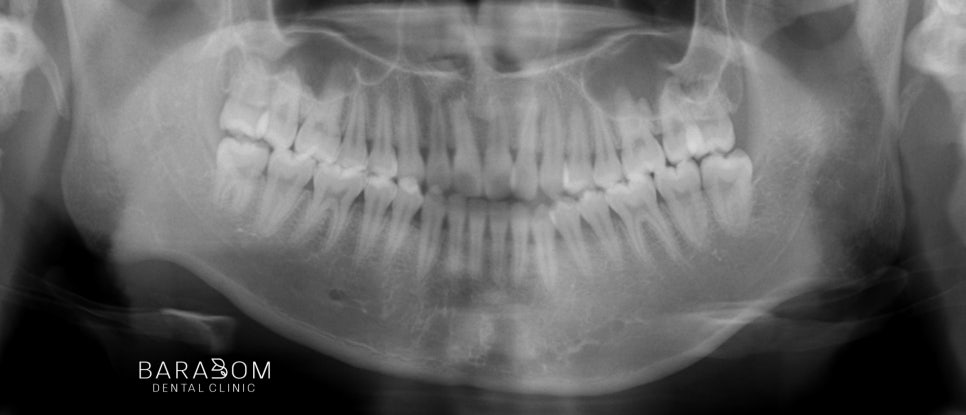

엑스레이 사진을 통해

4군데 모두 사랑니가 있는 것이

확인되는데요,

아랫턱 전체 치열을 후방으로

이동하기 위해서는 발치가 필요합니다.

그래야 뒤로 움직일 수 있는

공간이 충분히 확보됩니다.